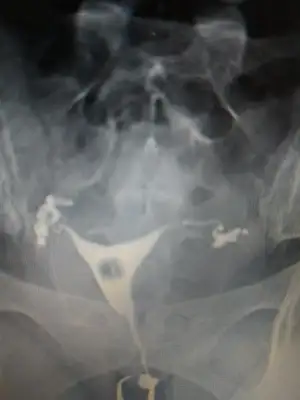

Onun hatlar karışık biraz. Çekim sonrası radyologun mesai saati bittiği için rapor yetişmemiş. Pazartesi alacak sonucunu. Kendi doktoru tüplerden birinde tıkanıklık var gibi konuşmuş ama başka doktorlara da göstermiş, basınçla açılmış demişler

pazartesi herşey sonuçlancak demek. Açılmıştır kuzum bak sorunun nerde olduğu anlaşıldı en azından en kısa zamanda gelecek beben